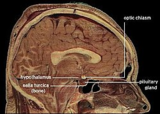

زیر نهنج یا هیپوتالاموس (به انگلیسی: Hypothalamus)، غده ای است در مغز، که دستگاه عصبی را با کمک غدهٔ هیپوفیز به دستگاه غدد درونریز متصل میکند.

هیپوتالاموس در اکثر پستانداران یافت میشود و خصوصیات متفاوتی در دو جنس مذکر و مؤنث دارد. هیپوتالاموس مانند بصل النخاع در تنظیم تنفس نقش دارد.

هیپوتالاموس از هسته های مختلفی تشکیل می شود.بخش قدامی یا سوپراکیاسماتیک،بخش میانی یا توبرال، بخش خلفی و بخش خارجی از قسمت های مختلف هیپوتالاموس هستند که هر بخش هسته هایی دارد.قسمت خارجی هسته های پره اپتیک خارجی و هیپوتالاموس خارجی را شامل می شود. هیپوتالاموس خارجی مرکز تنظیم و تحریک گرسنگی است و اختلال در عملکرد آن باعث بی اشتهایی و لاغری می شود.هسته های...